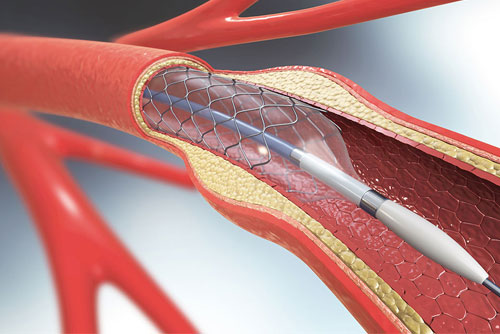

Carotid Stenting

Intracranial Stenting